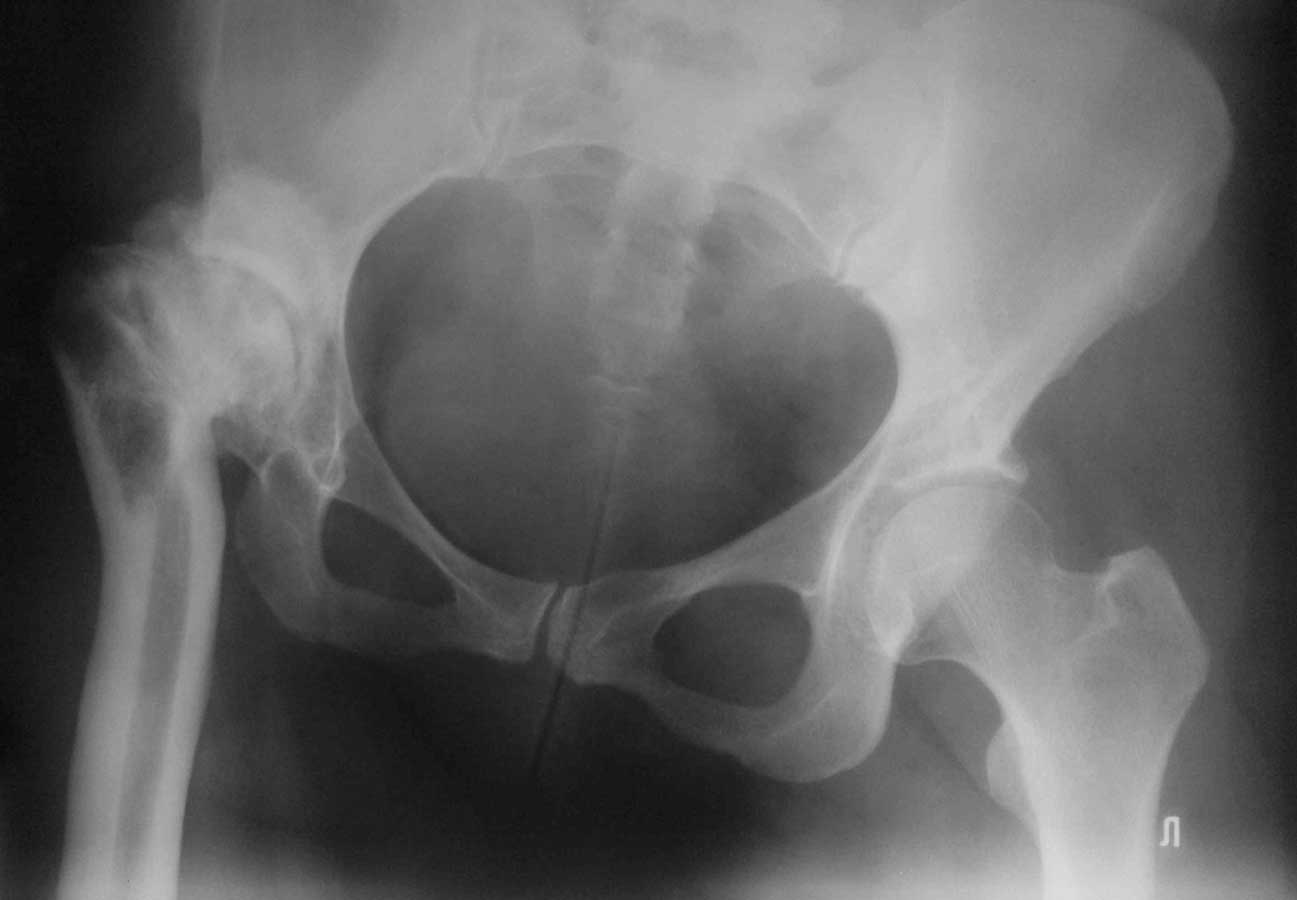

Уважаемые коллеги, к нам поступила женщина 45 лет с такой вот ситуацией: Операция около 1,5 месяцев назад: тотальное б/ц эндопротезирование с остеотомией проксимального отдела бедра. Послеоперационный период - без особенностей, рана зажила первично, выписана домой. В анамнезе в детском и юношеском возрасте несколько оперативных вмешательств на вертлужной впадине и бедре по поводу врожденного вывиха бедра, судя по рубцам, протекавшие не совсем гладко. около 2,5 недель назад пациентка начала отмечать вечерние подъемы температуры до 38. примерно в это же время выявлен высокий тромбоз поверхностной бедренной и общей бедренной вен, несмотря на прием антикоагулянтов. Пунктирован сустав - получен рост золотистого стафилококка. Учитывая острый тромбоз, назначена супрессивная а/б терапия с учетом чувствительности. В настоящее время: тромбоз с положительной динамикой с признаками реканализации, небольшой лейкоцитоз, СРБ до 12, вечерние свечки до 38 (не каждый день), субъективно - чувствует себя лучше. Локально: плотный отек в области п/о рубца, гиперэмия, небольшое количество пузырей с серозным отделяемым (сожалею, сегодня не успел сфотографировать). Вопросы: -какова вероятность локализации процесса в мягких тканях или не стоит выдавать желаемое за действительное? - объем ревизионного вмешательства: сохранять эндопротез или нет? одноэтапно или двухэтапно? На фоне остеотомии бедра испльзовать цементный спейсер или поробовать импакционную пластику с добавлением антибиотика или пластику - дистально, цемент проксимально?

1. Если материал получен из сустава, и конец иглы "нащупывал" компоненты протеза или кость - это перипротезная инфекция.

2. Бедренный компонент не выглядит стабильным, и стабильным на протезе с прокимальной фиксацией быть не может. Антиротационная пластинка слегка удерживает дистальный отломок, а плоскость остеотомии сложно назвать хорошо адаптированной. Из чего следует - бедренный компонент удалять. Вертлужный, если стабилен, можно оставить с заменой вкладыша

1. не факт, что материал получен точно из сустава

Не знаю как другие, но по выложенным рентгенограммах можно заподозрить лизис вдоль медиальной стенки дистального фрагмента. То что проксимальный фрагмент стабилен сомнений нет, по поводу дистального - как то сомнительно.

Конечно, гадать на таком рентгене - стабильны компоненты или нет - все равно что на кофейной гуще, можно сделать рентген в двух проекциях и без ротации ножки. Но точно определить можно лишь на ревизии. Будешь убирать или нет, спейсер или пластика или что-то еще(кто-то писал о вакуумном ведении протезной раны в течении недели после ревизии и дебридмента) - дело другое, но ревизовать надо. чем раньше тем лучше.